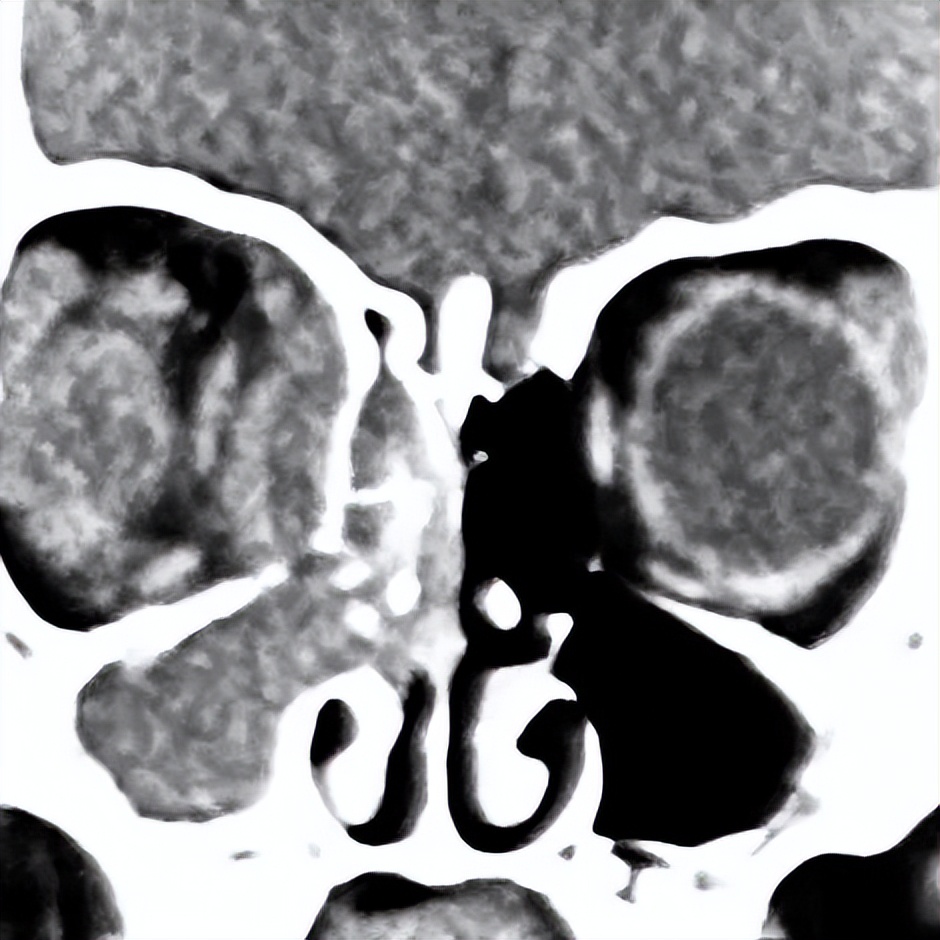

手术后,多学科专家团队密切观察患儿病情变化,每日进行查房讨论。术后第1天,患儿的体温和血液感染指标恢复正常,第2天查房时,小姑娘就在病房里睁着水灵的大眼睛和妈妈玩游戏了。

图 | 术前(左)与术后(右)对比